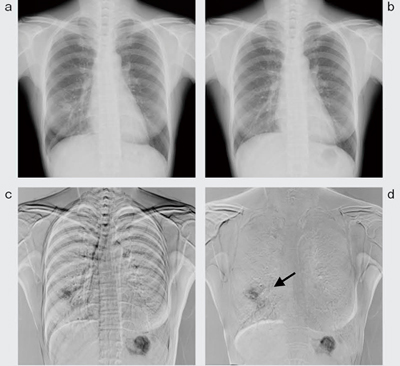

現在画像と過去画像は,被写体の撮影体位(前後屈,側屈)や息止めの位相の違いで,被写体全体の位置や血管・骨などの各臓器の位置が一致しないため,単純な差分処理では位置ずれアーチファクト(偽像)が発生しやすい。アーチファクトが生じると,経時的変化のある部分の検出が困難となる。ワーピング処理(図2,3)は,現在画像の対応位置に一致するように,過去画像を局所領域ごとに変形させてから差分する方法で,アーチファクトが大幅に軽減する。

図3 経時差分の実際

a:現在画像 b:過去画像

c:単純差分画像

d:ワーピング処理後差分画像。cに比べ,鎖骨,肋骨,心血管のアーチファクトが消失し,右下肺野の新たに出現した病変のみが明瞭に描出されている(←)